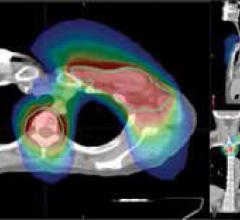

The nonprofit healthcare provider Swedish Medical Center (SMC) has been serving the Seattle area for more than 100 years. It has locations in both the city of Seattle and its surrounding suburbs, providing care in specialty areas such as cardiology, neuroscience, orthopedics, pediatrics and more. An integral part of the community, Swedish is unique in that it offers both technologies from Accuray, the TomoTherapy System and the CyberKnife System, for treating cancer patients in the metropolitan region.

Erlanger Health System in Chattanooga, Tennessee, purchased a CyberKnife Robotic Radiosurgery System in December 2010 to develop a stereotactic body radiation therapy (SBRT) program in its Radiation Oncology Department. The CyberKnife System included the Lung Optimized Treatment (LOT) function, which provides fiducial-free SBRT of early-stage lung cancer patients by enabling a hybrid method of spine tracking and tumor density tracking. Once the CyberKnife System was in use, the clinical team at Erlanger collaborated with referring physicians to explain to thoracic surgeons and pulmonologists — at Erlanger and other hospitals in the community — how the system could be utilized as a treatment option for their patients.

UT Southwestern Medical Center Kidney Cancer Program investigators have published what is believed to be the first reported successful use of stereotactic body radiation therapy for an often-deadly complication of kidney cancer.